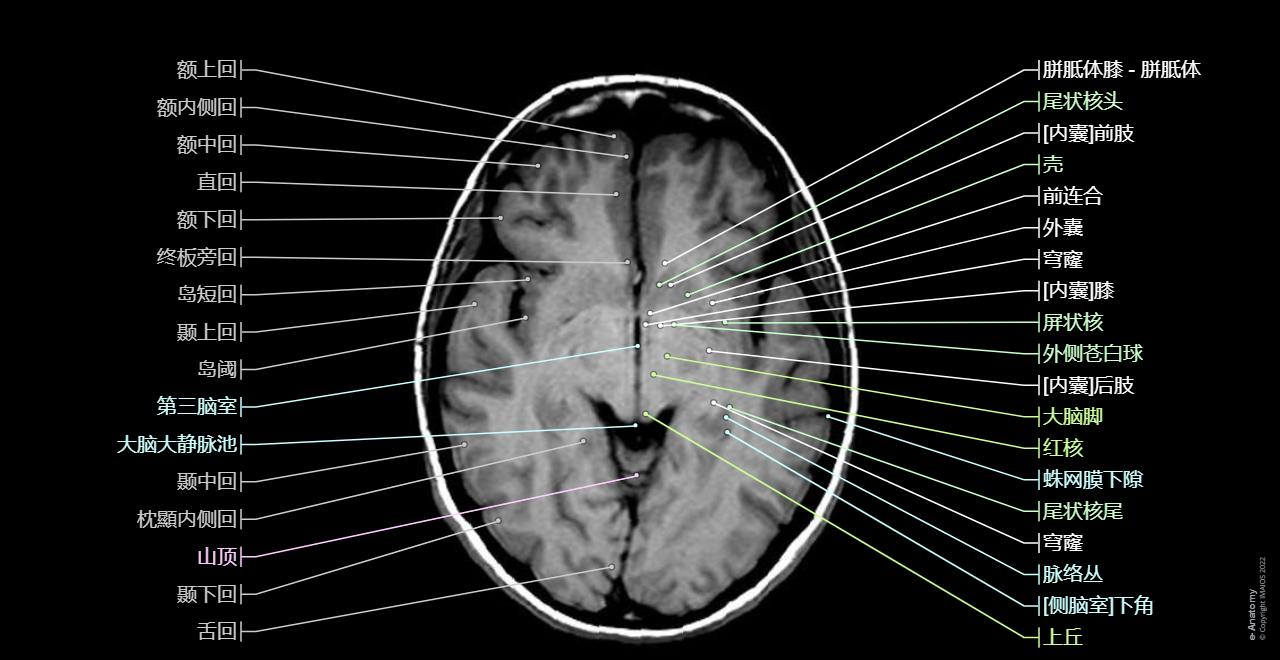

CAFEINTM项目

CAFEINTM项目最初是CERN为检测大型强子对撞机(LHC)等粒子加速器运行中的异常而开发的AI系统[351]。如今已被用于改善欧洲范围内的中风患者治疗结果。

110万

年受益中风患者数量

脑部MRI医学影像